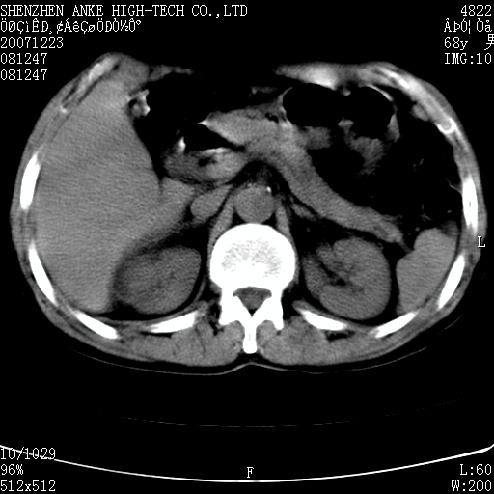

患者:男,63岁,2年前胆囊切除术后,现右上腹部剧烈疼痛近2天.

有无外伤史?右肾包膜下血肿可疑。

主要是问右肾有没有问题?患者无明显外伤史.

未见异常,病人差闭气,伪影较多.

上腹部ct平扫未见明显异常。

肠道准备不好,胃底后壁显示不清,右肾改变考虑为伪影。

请看第一张正位片,胸主动脉象有扩张,胸主动脉瘤?